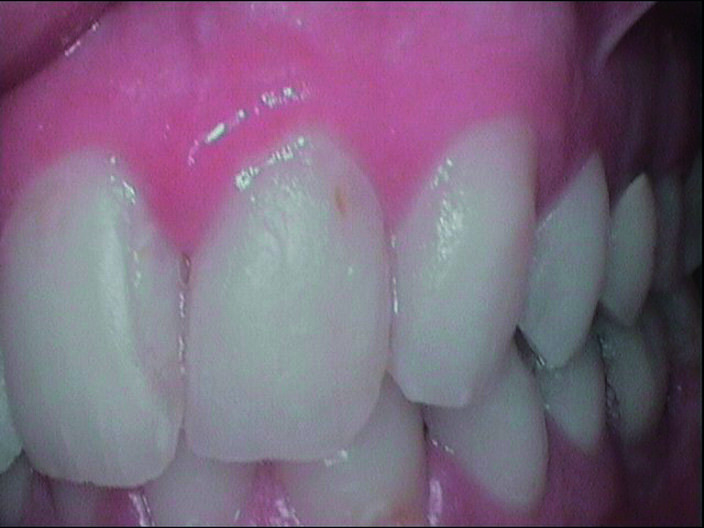

Durante l’esame obiettivo (Figg. 1a, 1b) rileviamo il danno iatrogeno da terapia ortodontica precedente alla visita e riscontriamo la presenza di processo carioso ICDAS 3 in zona 33 e in zona 47, white spots in zona 31 e 41. Durante l’esame obiettivo, l’ausilio della videocamera intraorale Sopro-Care (Acteon) permette, tramite filtri appositi, di evidenziare in modo rapido e accurato le zone di demineralizzazione e le aree infiammate e di mostrarle al paziente in real time, rendendolo attivamente partecipe e consapevole della situazione clinica (Figg. 2a-2f). I ricercatori del Baylor College of Dentistry hanno dimostrato che il 23,4% dei pazienti ha sviluppato almeno una white spot lesion durante il trattamento ortodontico.

Chiediamo al paziente se si fosse sottoposto a terapia ortodontica e il paziente riferisce di essersi sottoposto a terapia ortodontica in età adolescenziale per circa 2 anni e di non aver dato molta importanza alle lesioni presenti, poiché non aveva avuto grande sintomatologia riteneva che le white spots presenti non fossero un segno di demineralizzazione. Alla domanda della causa delle lesioni riferiamo che un inefficace controllo di placca domiciliare e uno stile di vita alimentare cariogeno, alzava il rischio di demineralizzazione delle lesioni che probabilmente erano state provocate dall’apposizione delle bande ortodontiche con materiale non di ultima generazione come i cementi vetroionomerici in grado di liberare fluoro. Inoltre riferiamo che durante la fase terminale del debonding, la topografia delle lesioni faceva presupporre l’uso poco attento di frese che avevano danneggiato lo smalto. Il paziente si mostra motivato e chiede una soluzione terapeutica che abbia come obiettivo la risoluzione funzionale ed estetica più veloce possibile. Viene condiviso con il paziente il piano terapeutico e proponiamo di iniziare con la terapia parodontale non chirurgica. Concordiamo con il paziente tempi, modalità di utilizzo e strumenti per migliorare il management degli stili di vita domiciliari, per il controllo chimico e meccanico del biofilm batterico (Nardi GM, Sabatini S, Guerra F, Tatullo M, Ottolenghi L. Tailored Brushing Method (TBM): an innovative simple protocol to improve the oral care. J Bio- med 2016; 1:26-31).